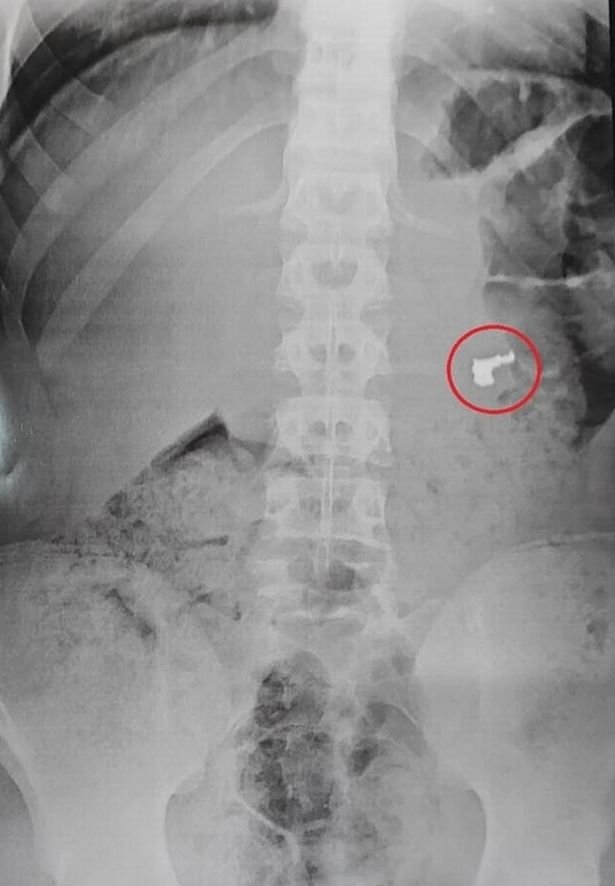

Bununla birlikte, tıbbi muayene yani röntgen esnasında şaşırtıcı bir durum ortaya çıktı. Zanlılardan birinin midesinde altın bir zincir bulundu. Gencin yaptığı hırsızlığın ardından yakalanmamak için kolyeyi yutması ise hastanedekiler tarafından şaşkınlıkla karşılandı.